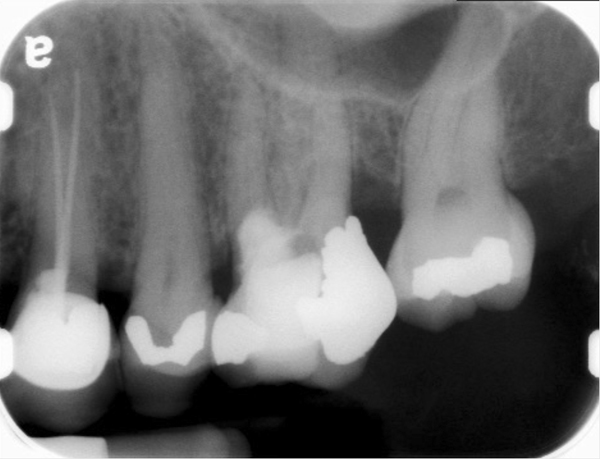

Clinical procedure: If apical bone loss is present (Figure 1) a collagen/gelatin sponge (eg, Gelfoam®, Pfizer Inc., www.pfizer.com) can be placed apically so that the MTA can be delivered to the desired working length. (Any other surgical resorbable sponge would also work, such as OraPlug® [Salvin Dental Specialties, www.salvin.com], Surgifoam® [Midwest Dental, www.mwdental.com], or Surgispon® [Aegis Lifesciences, www.surgispon.com]). This is done by taking a small piece (2 mm x 2 mm) of the resorbable sponge and pushing it down to and through the root apex with an endodontic file. Once this is done, MTA is packed down the canal with a custom-fitted cone. The clinician can use a rubber stopper on the gutta-percha cone to know the exact length of MTA placed in the apical third (Figure 2). Once the apical third is sealed with 3 mm to 5 mm of MTA, the remaining coronal canal space can be back-filled using a warm gutta-percha technique (Figure 3).

Fig 1. Preoperative radiograph showing apical bone loss.

Figure 1

Fig 2. MTA placed in the apical third.

Figure 2

Fig 3. Postoperative radiograph.

Figure 3